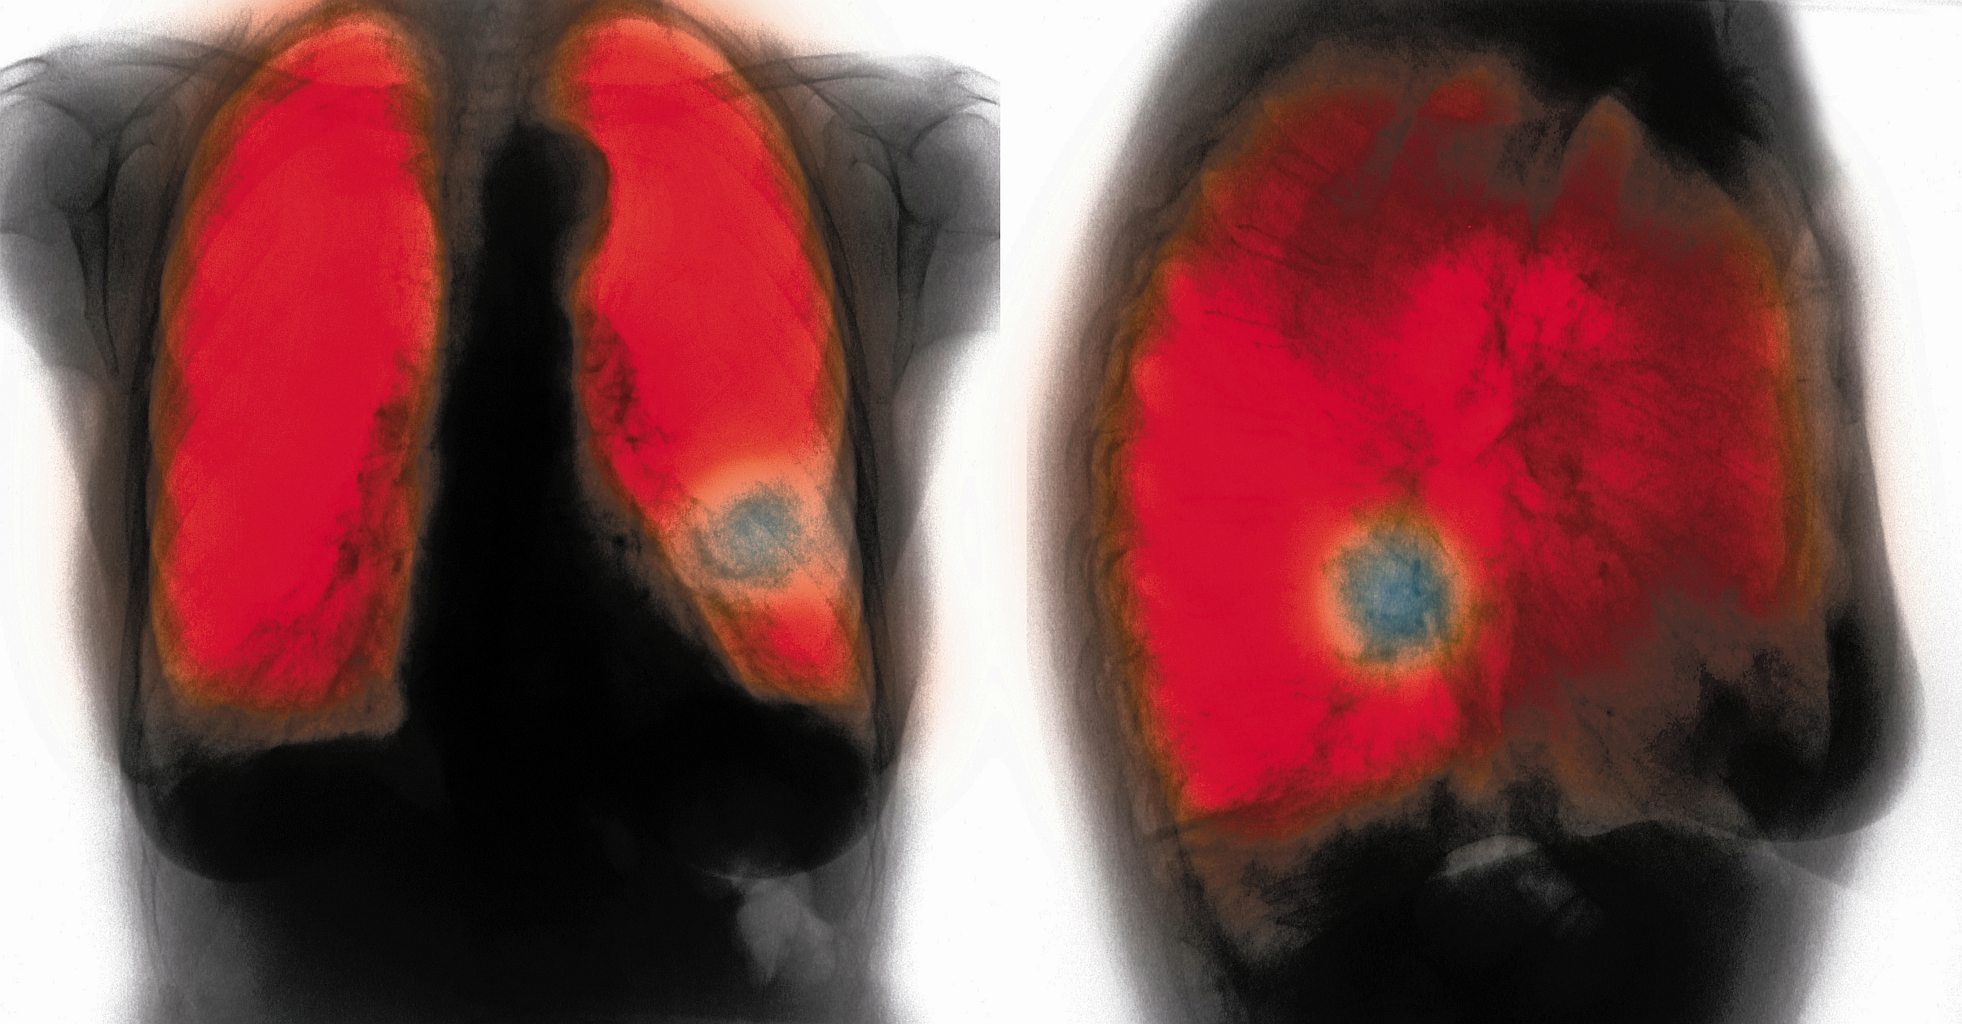

Rozdęte pecherzyki płucne i zwężone drobne oskrzeliki, w których rozwija się stan zapalny.SPL/East News Rozdęte pecherzyki płucne i zwężone drobne oskrzeliki, w których rozwija się stan zapalny.